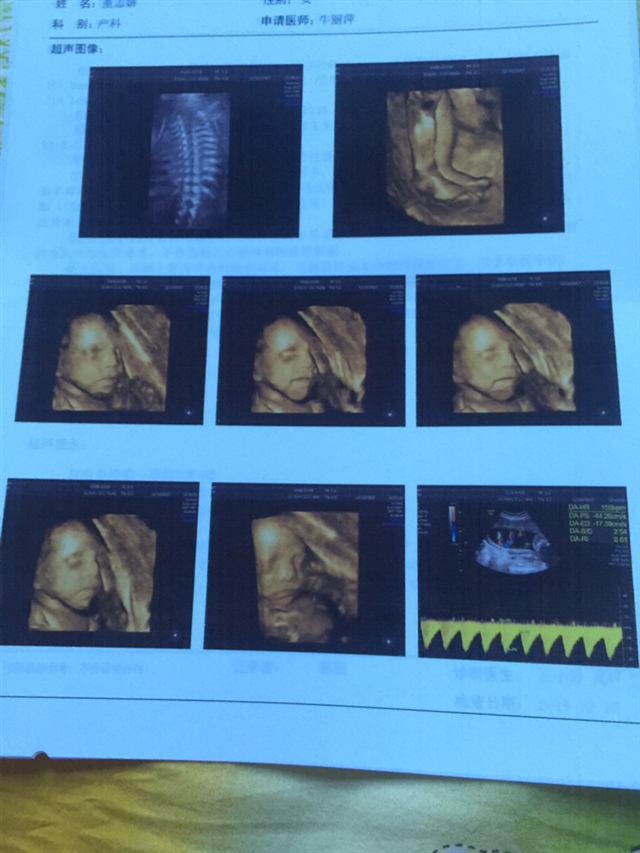

宝宝2个月16天

感觉像男宝宝

我前几天看过一个四维彩超的照片,宝宝恰好匹着腿露着小鸡鸡😂现在生个娃太不容易啦,不管男娃女娃,大人娃娃都平安健康就好。我是没啥要求。

我怎么没看见小鸡鸡。是女娃娃嘛?😄

baby[帖主]:医生不拍那里,避重就轻^_^